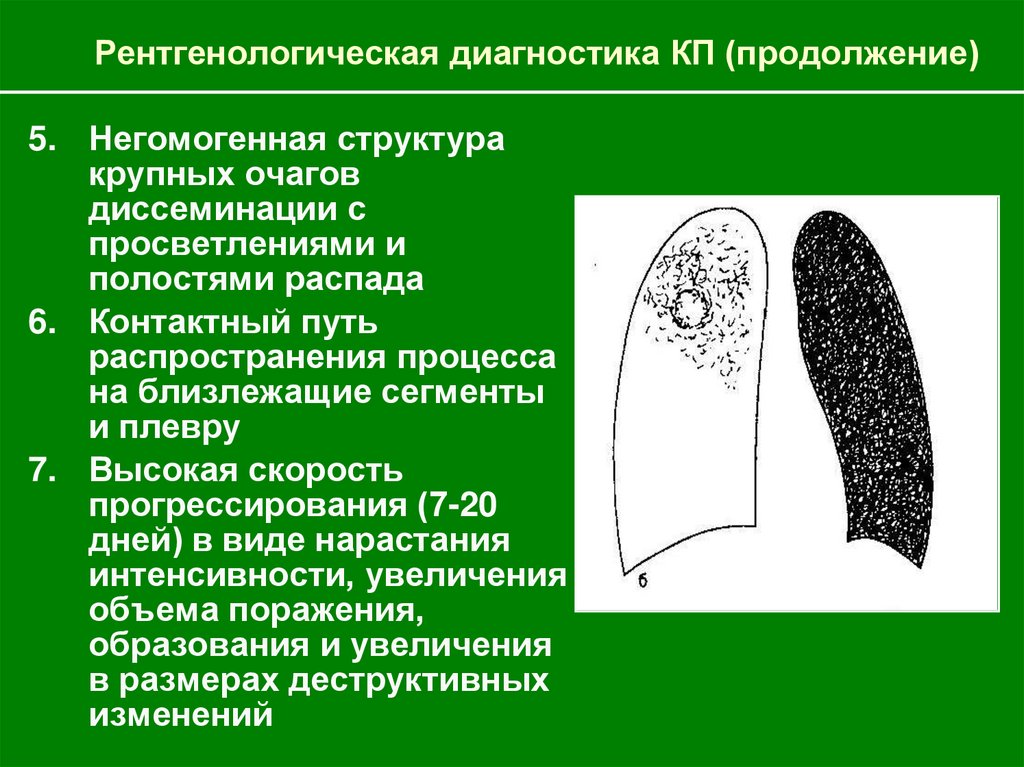

Очаговый и инфильтративный туберкулез презентация - 94 фото